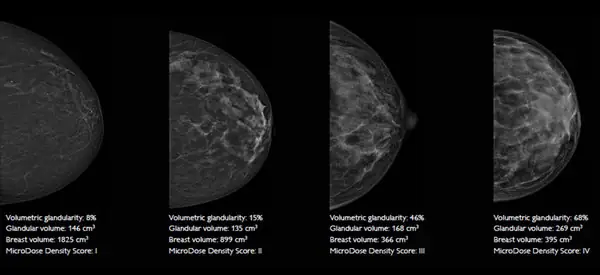

В системе MicroDose SI реализовано первое спектральное приложение компании Philips — функция измерения плотности молочной железы Spectral Breast Density Measurement.

Данная функция использует различия в энергетическом спектре жировой и железистой тканях для их дифференциации.

Это позволяет проводить точные измерения объемной плотности молочной железы и открывает новые возможности для улучшения оценки рисков и выработке индивидуального подхода к каждой пациентке.

Функция Spectral Breast Density Measurement использует спектральную информацию, полученную из обычной низкодозной маммограммы для:

расчета объема и объемной процентной доли железистой ткани;

присвоения изображению показателя плотности ткани, который согласуется со шкалой BI-RADS® для состава тканей молочной железы, что экономит время при анализе изображений;

Точные спектральные измерения объемной плотности тканей молочной железы

Расчет объективного показателя плотности, согласующегося со шкалой BI-RADS для состава тканей молочной железы